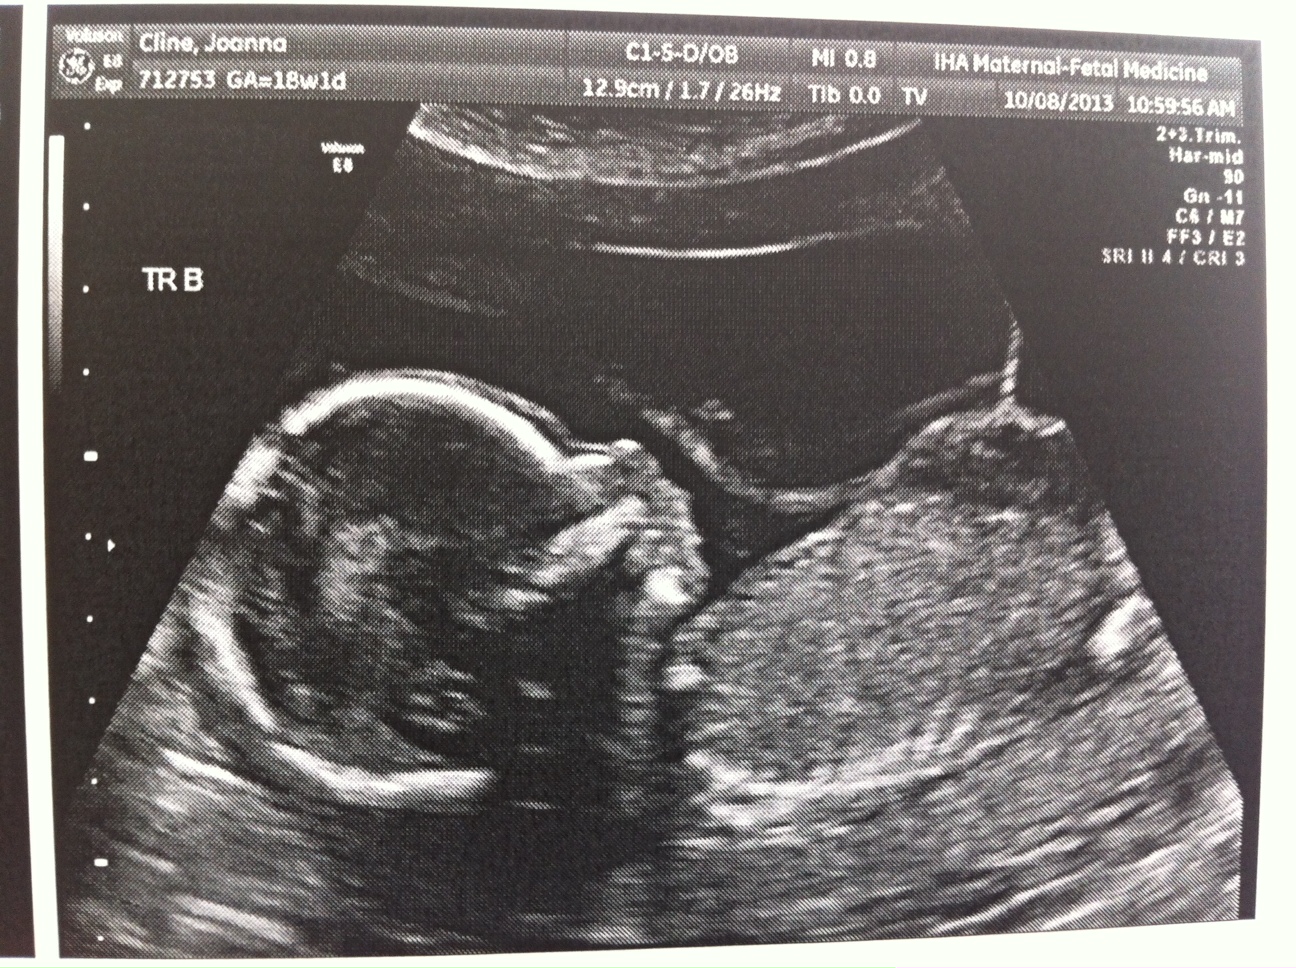

Everything still looks great. The triplets are growing but we won’t have another growth scan until my 22wk appointment. Heart beats look good and it’s clear they’re getting bigger (Today’s pictures attached.)

I’m feeling movement but mostly from triplet B. My dr said to just give it a few weeks and it will feel like a conga line in my belly.